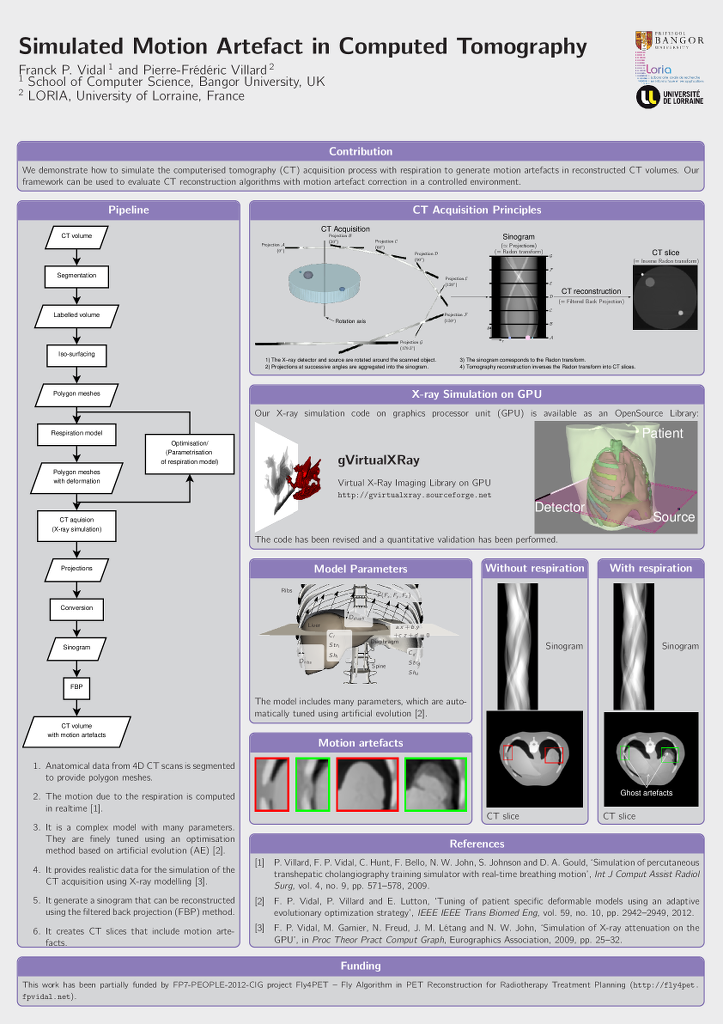

Franck P. Vidal and Pierre-Frédéric Villard.

Simulated Motion Artefact in Computed Tomography.

In Katja Bühler, Lars Linsen, and Nigel W. John, editors,

Eurographics Workshop on Visual Computing for Biology and Medicine, pages

213--214. The Eurographics Association, 2015.

Franck P. Vidal and Pierre-Frédéric Villard.

Simulated Motion Artefact in Computed Tomography.

In Katja Bühler, Lars Linsen, and Nigel W. John, editors,

Eurographics Workshop on Visual Computing for Biology and Medicine, pages

213--214. The Eurographics Association, 2015.

| |

We propose a simulation framework to simulate the computed tomography acquisition process. It includes five components: anatomic data, respiration modelling, automatic parametrisation, X-ray simulation, and tomography reconstruction. It is used to generate motion artefacts in reconstructed CT volumes. Our framework can be used to evaluate CT reconstruction algorithm with motion artefact correction in a controlled environment. |